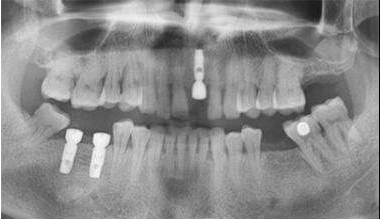

CBCT拍攝,進(jìn)行牙槽骨厚度、寬度和高度的測量。

檢查需拔除的牙根,判斷是否符合種植的條件。

根絕骨質(zhì)量的情況,提前選擇是否需要數(shù)字化種植導(dǎo)板。